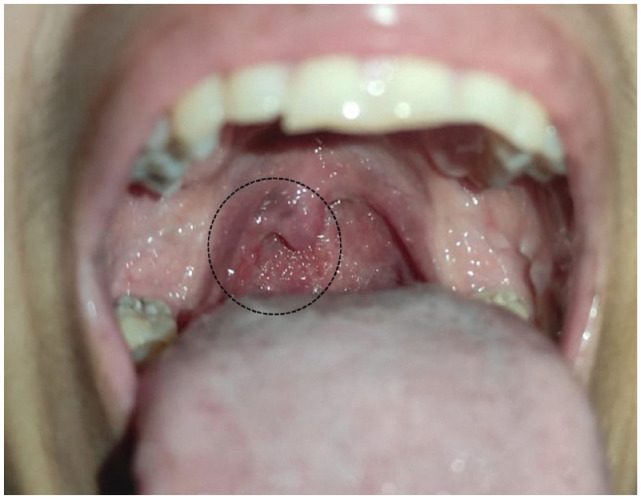

Pharyngeal tuberculosis without pulmonary involvement is very rare and may be confused with malignant lesions. We present a 45-year-old female patient with a history of HIV presenting with a history of cough, sore throat, and oral ulcers with chronic use of antibiotics. The evolution would indicate a probable malignant tumor, but the biopsy was consistent with Pharyngeal TB. The patient initiated anti-tuberculosis therapy and demonstrated improved conditions and remission of ulcers. In the context of HIV, this treatment could be a major contributor to the underdiagnosis of the disease and may lead to alternative diagnoses. Therefore, it is vital to consider this condition in patients who do not respond to antibiotics.